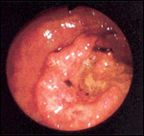

A flat, ulcerated adenocarcinoma